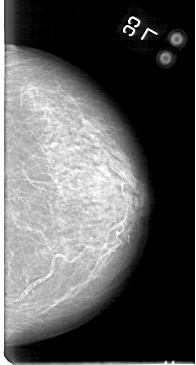

D_4044_1.LEFT_MLO

LEFT_MLO LINES 5386 PIXELS_PER_LINE 2956 BITS_PER_PIXEL 12 RESOLUTION 43.5 NON_OVERLAY